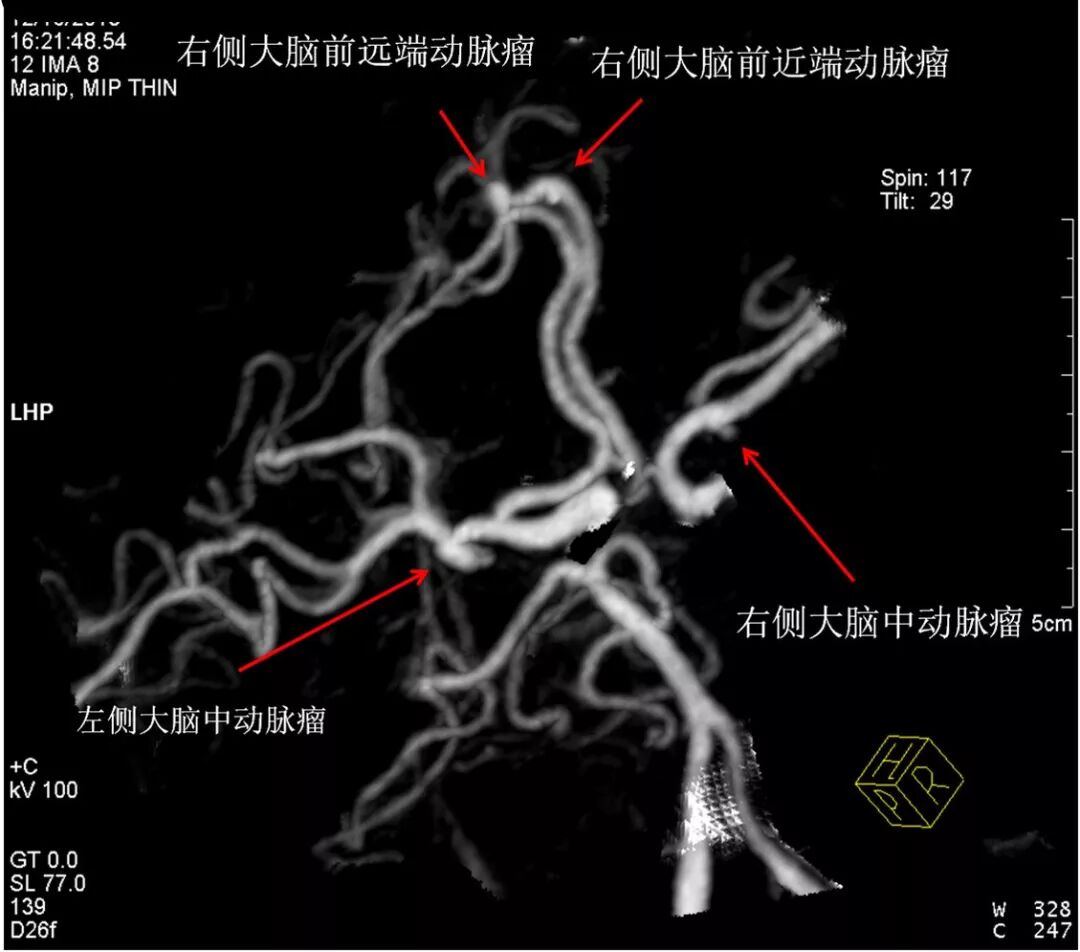

头颅CTA示:

左右双侧大脑中动脉瘤(镜像动脉瘤)+右侧大脑前2枚动脉瘤。根据CT及CTA影像,考虑右侧大脑中动脉动脉瘤破裂,为责任动脉瘤。